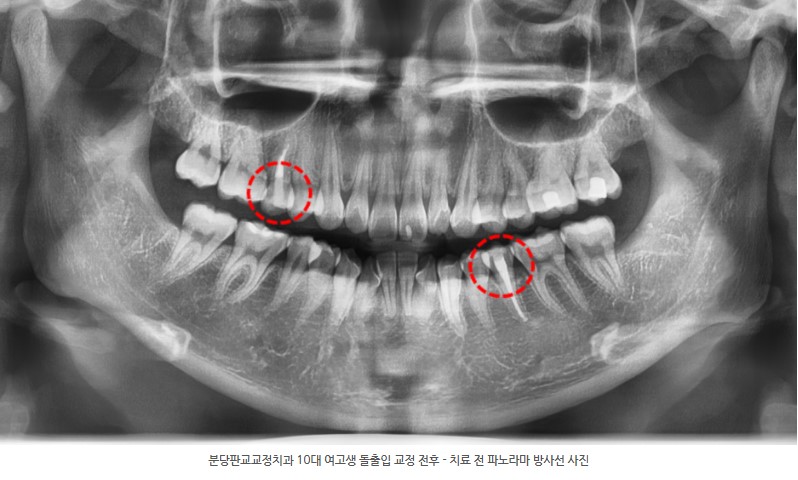

정밀 진단(구내 검사, 파노라마 X-ray 등) 결과, 다음과 같은 문제점이 확인되었습니다.

검사 결과, 상악 우측과 하악 좌측의 제2소구치는 이미 신경치료가 완료된 상태였습니다.